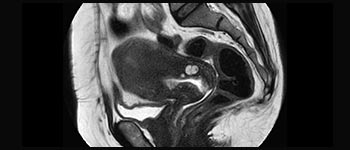

Female Pelvis overview